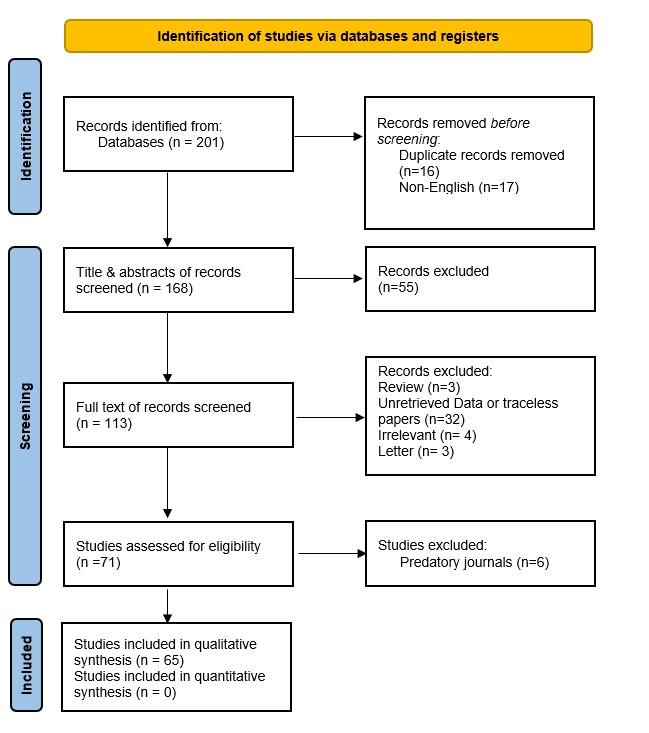

Thyroid function assessment revealed that the majority (7 cases ,63.6%) of patients were euthyroid (0.35-4.5µIU/mL), while two patients exhibited hyperthyroidism (<0.35 µIU/mL), and two of them had hypothyroidism (>4.5 µIU/mL). Ultrasound findings demonstrated left lobe and isthmus agenesis in eight cases (72.7%), while two cases (18.2%) exhibited isolated left lobe agenesis, and one patient exhibited isolated right lobe agenesis (9.1%) (Figures 1 and 2). The largest documented normal lobe measured 100 × 43 × 35 mm, whereas the smallest measured 15 × 6.9 × 7.9 mm. The follow-up period ranged from 4 to 48 months (Tables 1-3).